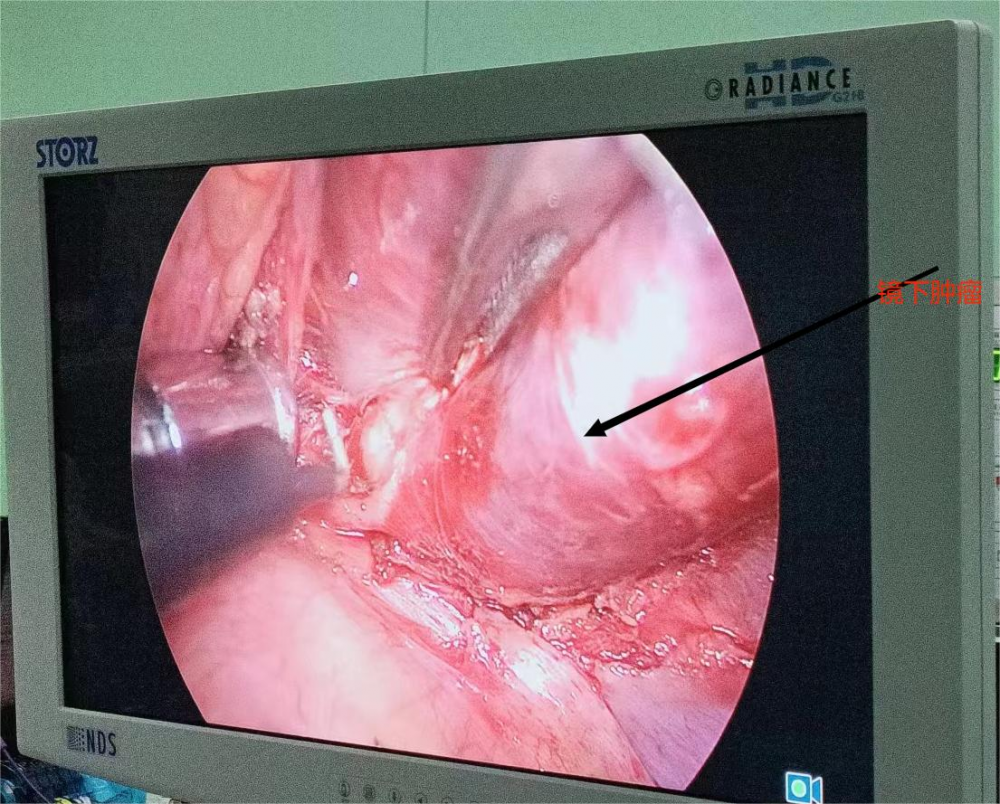

術中顯示腫瘤位置

患者,孫×軍,中年男性。 6月22日,查體發(fā)現(xiàn)左前上縱隔胸頂處占位,考慮神經(jīng)源性腫瘤,遂來我院胸外科要求手術治療。胸外科主任季運來看過該患者后,通過認真仔細評估,初步診斷患者為神經(jīng)源性腫瘤。該腫瘤位于胸頂部胸廓入口處,即血管神經(jīng)的出入口處,與無名靜脈、交感神經(jīng)等大血管、神經(jīng)聯(lián)系密切,如不及時做手術、則很快出現(xiàn)腫瘤壓迫血管、神經(jīng)(Horner綜合征)等并發(fā)癥。手術切除病變是其唯一切實有效的治療方法。 與患者及家屬充分溝通后,擬訂為其實施胸腔鏡下腫瘤切除術。手術邀請北京協(xié)和醫(yī)院專家來院指導。6月28日,手術經(jīng)過2個多小時,在全胸腔鏡下成功切除該腫瘤。術后患者恢復順利,未出現(xiàn)Horner綜合征等任何并發(fā)癥,于7月4日康復出院。該手術的順利完成,標志著我院胸外科胸腔鏡技術又上了一個新臺階,真正為胸腔縱膈疾病患者帶來福音。